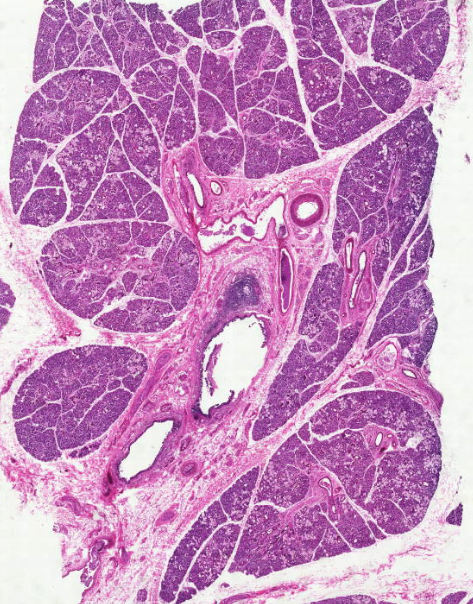

Поперечнополосатая мускулатура, Рыхлая волокнистая ткань

Skeletal muscles, loose areolar connective tissue

ماهیچه اسکلتی/بافت پیوندی سست